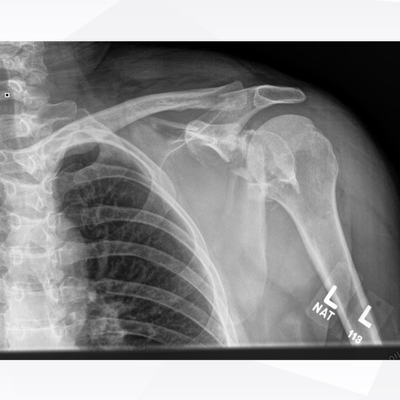

Click on an image below to view more info.